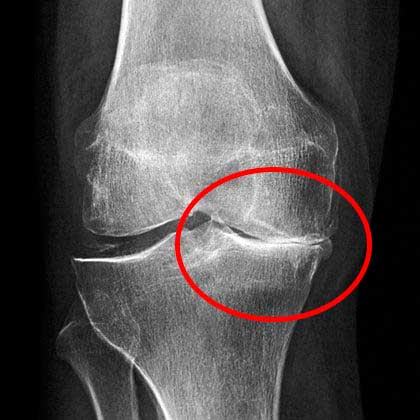

ตอนไปพบหมอครั้งแรก หมอใช้เวลานานมากในการดูภาพเอ็กซ์เรย์ แล้วบอกว่าให้ฉันเลิกทำงานหนักๆได้เลย และห้ามยกของหนักเกิน 2 กิโลกรัม

ภาพเอ็กซ์เรย์แสดงให้เห็นว่าเข่าของฉันมีปัญหาร้ายแรง